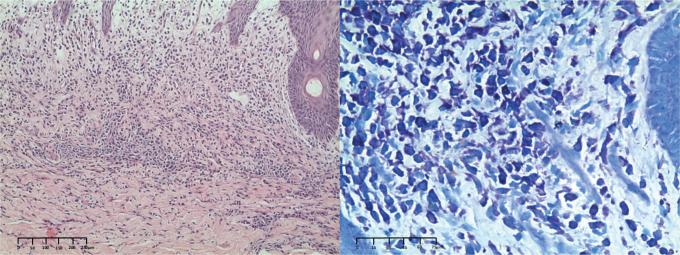

A 9-month-old Child with Diffuse Cutaneous Bullous Erythema: A Quiz.

https://cdn.ncbi.nlm.nih.gov/pmc/blobs/2f31/12382381/26dc85ff1699/ActaDV-105-43939-g001.jpg